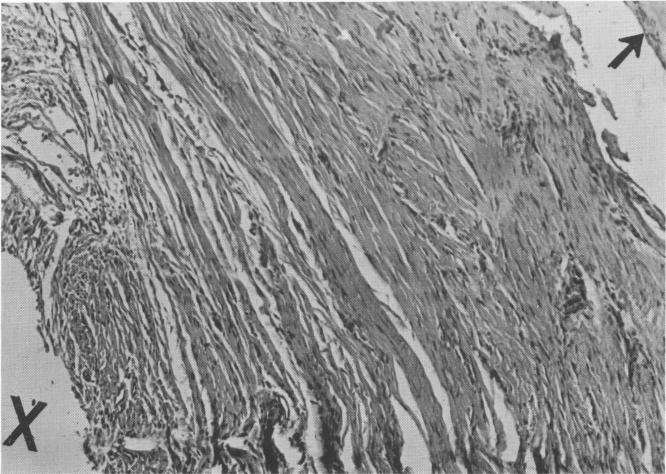

Fig. 4-31. The connective tissue around the successful implant was characterized by its density and regular organization (cross section; high power). X, Implant site; arrow, bone formation.

2 Dense and regular connective tissue near Chercheve spiral post implant